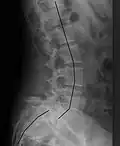

X-ray of the lateral lumbar spine with a grade III anterolisthesis at the L5-S1 level | |

Spondylolisthesis is graded based upon the degree of slippage of one vertebral body relative to the subsequent adjacent vertebral body.[6] Spondylolisthesis is classified as one of the six major etiologies: degenerative, traumatic, dysplastic, isthmic, pathologic, or post-surgical.[7] Spondylolisthesis most commonly occurs in the lumbar spine, primarily at the L5-S1 level, with the L5 vertebral body anteriorly translating over the S1 vertebral body.[7]

Classification by degree of the slippage, as measured as percentage of the width of the vertebral body:[17] Grade I spondylolisthesis accounts for approximately 75% of all cases.[7]

- Grade I: 0–25%

- Grade II: 25–50%

- Grade III: 50–75%

- Grade IV: 75–100%

- Grade V: greater than 100%